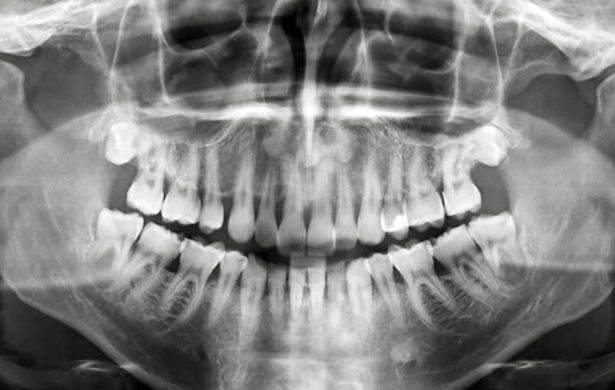

Panoramic X-Ray

Cone Beam Imaging

Cone Beam imaging is an advanced form of digital radiograph. With the cone beam imager, one simple scan will produce a 3D image of your entire maxillofacial structure. This image can then be used in diagnostics, patient education, treatment planning, and treatment follow-up.

The cone beam provides an effective solution to create quick, clear, precise images for your benefit. Additionally, the cone beam uses minimal radiation in scanning and is a much less-invasive process than other forms of imaging. This makes the cone beam an excellent choice for patients with dental anxiety or a sensitive gag reflex.

By utilizing advanced technologies like the cone beam, we can provide an effective, efficient, and comfortable patient experience for you on every visit.